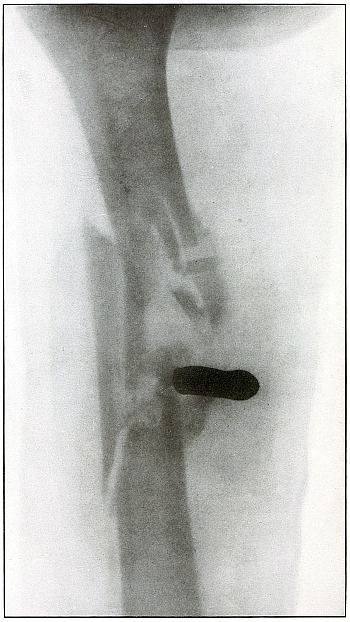

Rifle—Plate 41.

UPPER EXTREMITY.

Gunshot Fracture of the Wrist.

Wound of entrance, posterior aspect of forearm over the lower end of the radius, with the bullet ranging forward and slightly downward to the wound of exit and covering with great laceration the anterior aspect of the wrist joint.

The range was close, and the energy of the high velocity of the missile was imparted to fragments, which, becoming “secondary missiles,” emerged with the projectile to cause extensive laceration and destruction of tissue.

The case was received for amputation in the second week, when a grave degree of infection extended in a cellulitis to the elbow. The ulnar nerve and vessels were intact, but the flexor tendons were almost entirely destroyed.

The plate, made after several weeks, when infection was under control and after the end of the radius and fragments of the carpus had been informally removed, shows a rarefaction of the carpus and proximal ends of the metacarpus, due to infection and disuse.

Frequent incisions and extension of drainage, with removal of detached fragments, was continued for several months. The wound was closed in the sixth month, with ankylosis and deformity of the wrist, as shown in plate 42. [Pg 94]